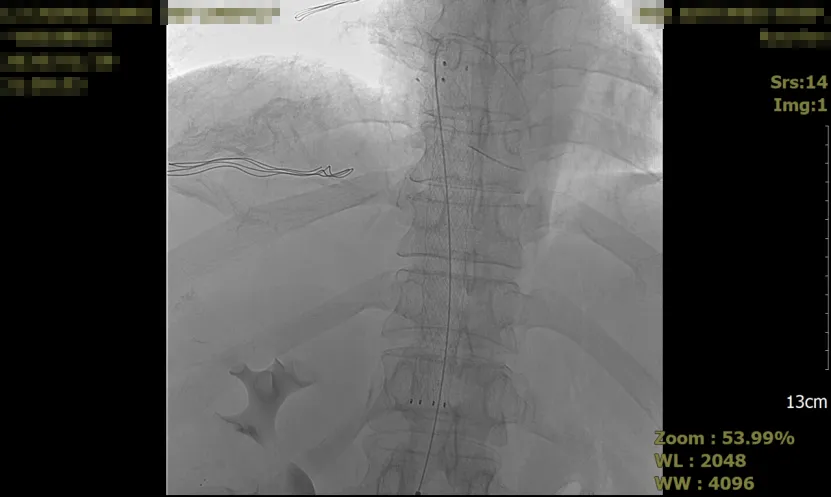

为防止血栓进一步迁移及加重症状,采取了介入治疗,具体措施包括:在2026年1月29日夜间,血栓取出,并植入支架以支撑血管通畅。

术后影像